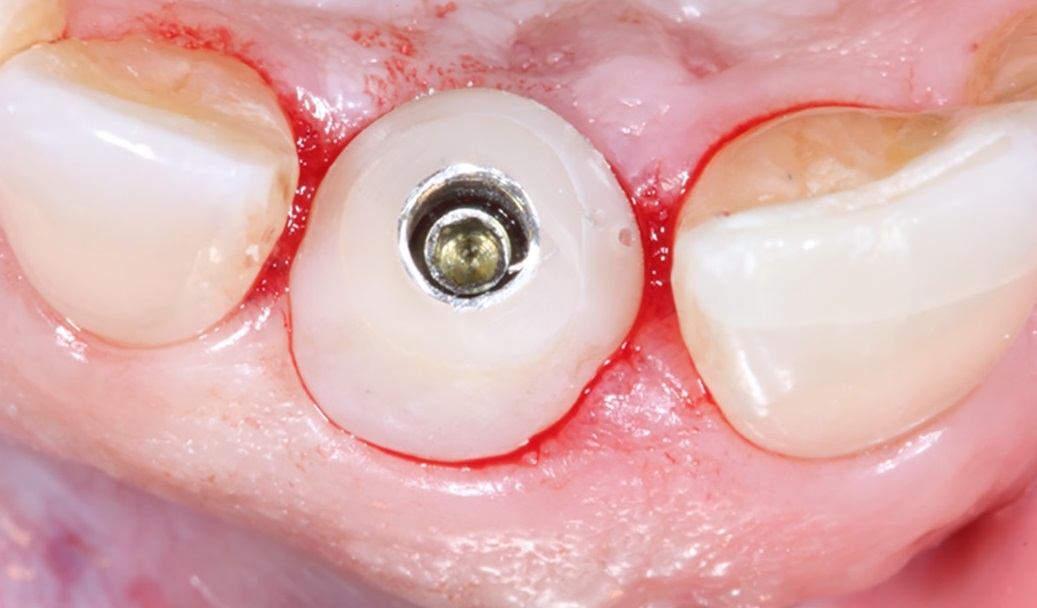

Bước 4: Đặt trụ phục hình cá nhân hóa lên miệng và gắn răng sứ.

Sau khi Scanning, dữ liệu được đưa về trung tâm thiết kế giả lập, trụ phục hình cá nhân hóa sẽ được sản xuất tại đây, sau khi sản xuất xong sẽ được gắn lên miệng, trụ phục hình thông thường sẽ được thiết kế trùng khít với cấu trúc mô nha chu.

Một răng sứ cũng sẽ được thiết kế và gắn lên trụ phục hình cá nhân hóa ở bước này.

Trụ phục hình cá nhân hóa bằng Zirconia

Hình ảnh gắn trụ phục hình và gắn răng sứ. Một trường hợp trồng implant răng cửa bằng giải pháp DCT tại Lạc Việt Intech.

• Bước 7: Gắn trụ phục hình các nhân hóa và răng sứ.

Trụ phục hình và răng sứ sau khi được sản xuất xong sẽ chuyển về phòng khám, bác sĩ sẽ hẹn bạn tới nha khoa để lắp trụ phục hình cá nhân hóa và răng sứ.

Đây là lần hẹn thứ 5 bạn tới nha khoa, lần hẹn này cách lần hẹn Scanning khoảng 5 ngày.